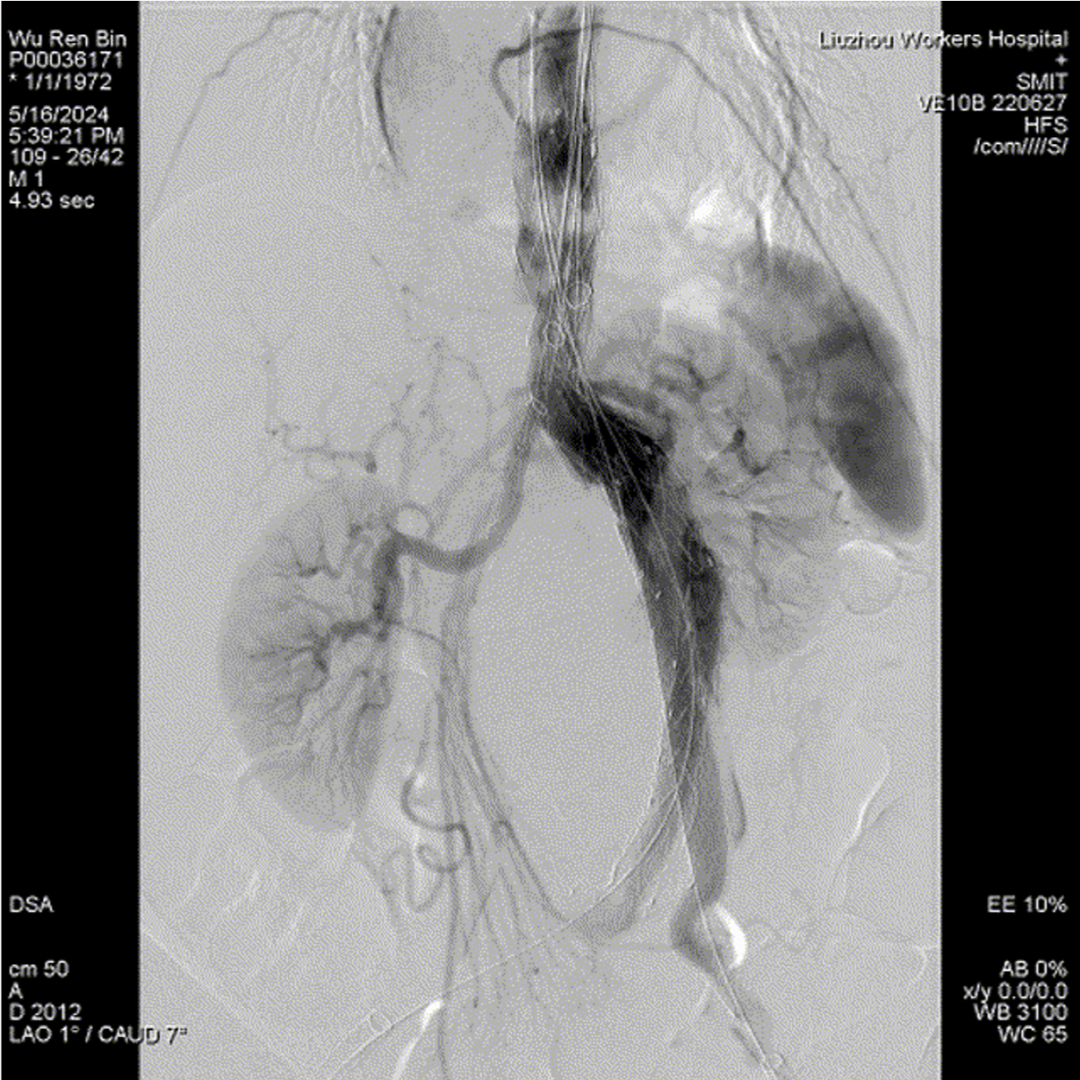

四分支重建后造影,各分支血流通畅

术前造影